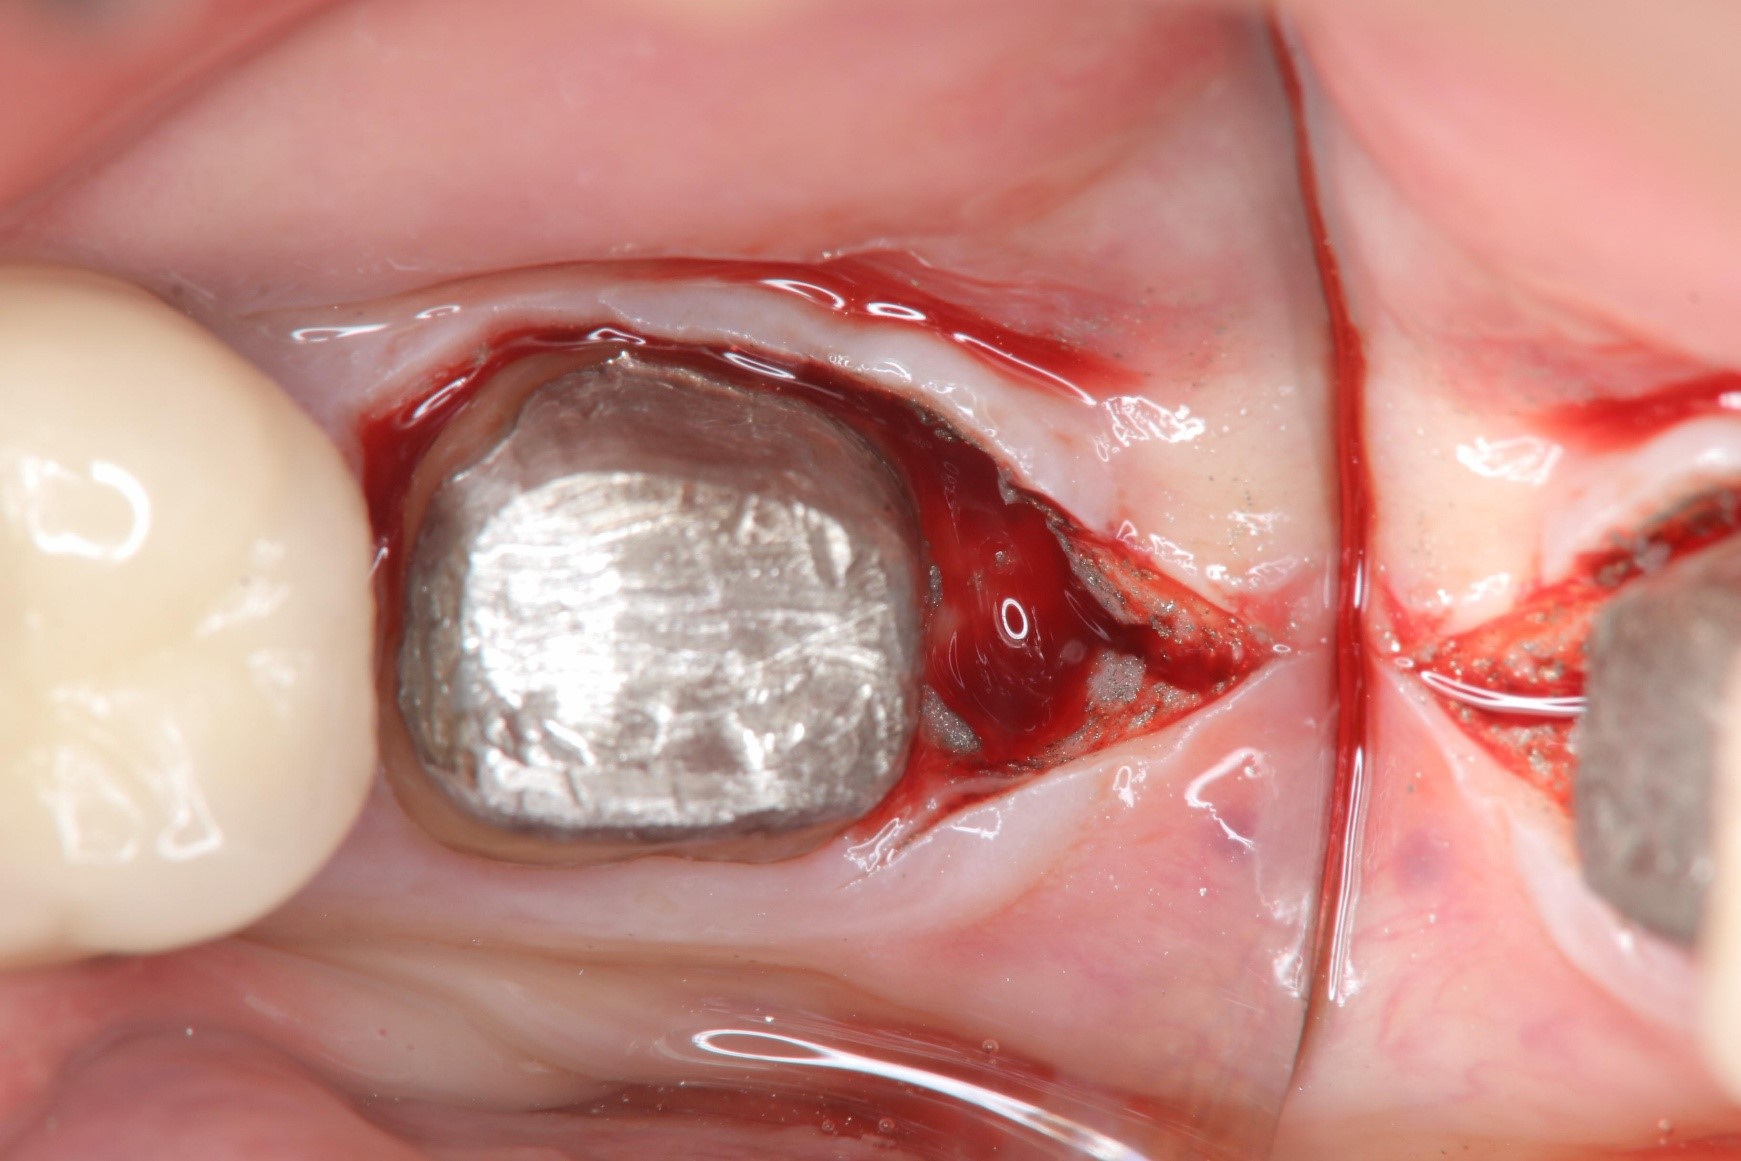

當牙齒齲齒部分過大或是牙齒大面積斷裂,導致臨床牙冠邊緣靠近牙齦或甚至在牙齦之下,表示臨床牙冠太短,不足以製作假牙。此時應當先執行牙冠增長術,來爭取更長的臨床牙冠以得到足夠的圍箍效應,假牙才不容易脫落。如不先執行牙冠增長術就貿然做上假牙,將造成牙齒的圍箍效應不足,假牙受力後容易脫落甚至整顆牙齒斷裂,以至於面臨需要將牙齒拔除的結果。

牙冠增長手術

牙齒印模前追蹤

因為齲齒或牙冠斷裂至牙齦下方,導致齒質不足、牙冠過短,以致無法有足夠的生物寬度或是圍箍效應,此為臨床上需要執行牙冠增長術的最常見原因。